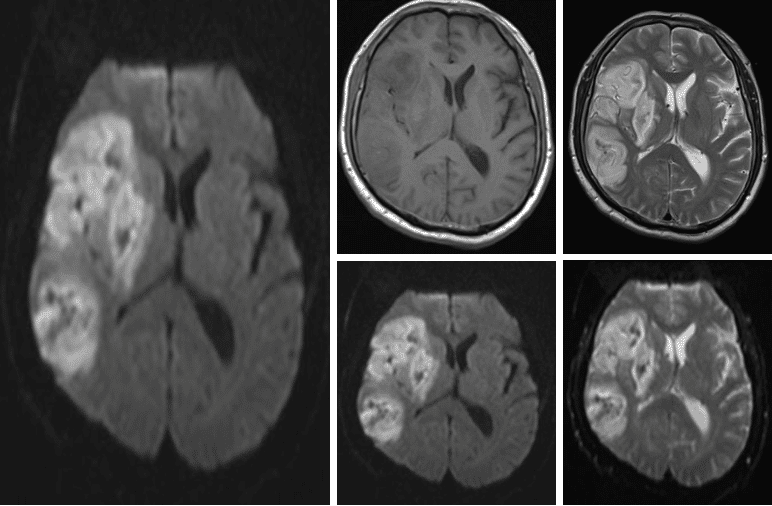

头MR(2023-09-16)示右侧额颞、放射冠区基底节区混杂信号,请结合CT或SWI检查。